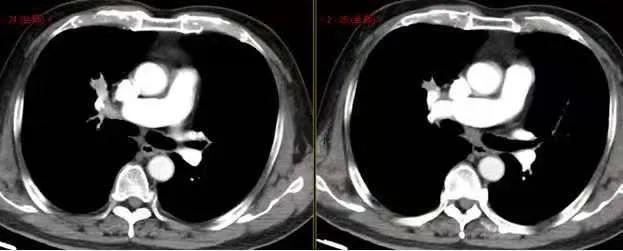

女 71 岁 发现左肺结节多年,无明显症状。

病灶圆润、光滑,增强无明显强化。